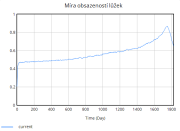

| 22:34, 15 June 2025 | 1 Obsazenost.png (file) |  |

13 KB | Kozo01 | 1 | |